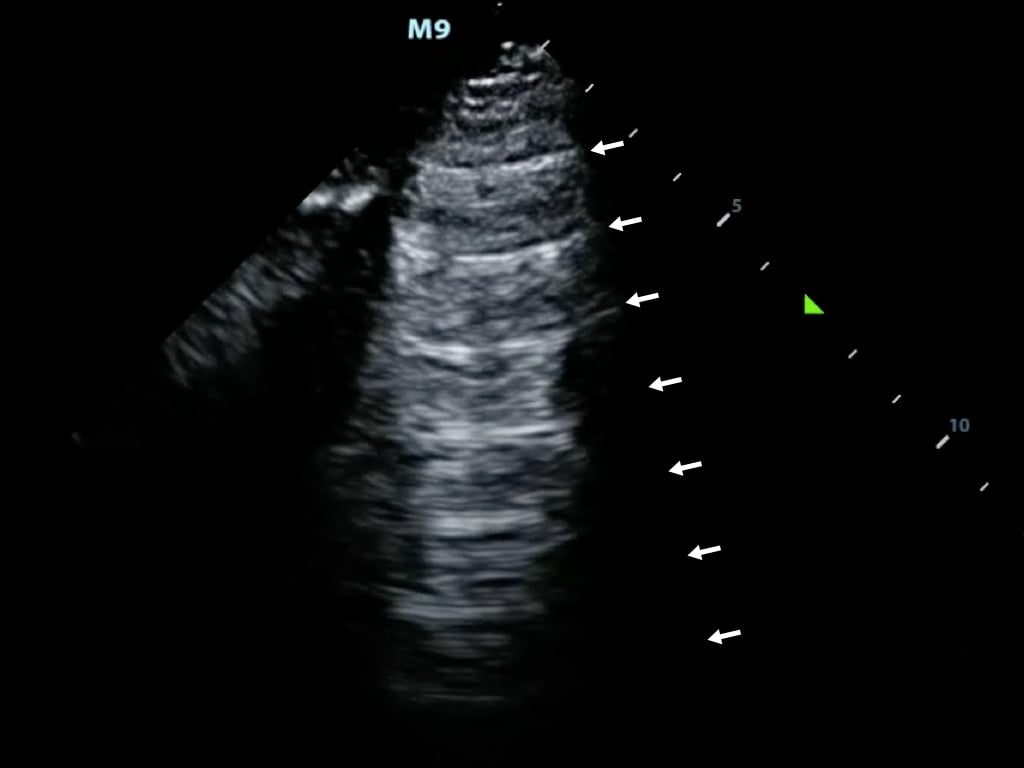

- M-mode (motion mode) captures returning echoes in only one line of the B-mode image displayed over time

- Movement of structures positioned in that line can now be visualized

- Often M-mode and B-mode are displayed together in real-time on the ultrasound monitor (Figure 2, Video 1)

- Figure 2. M-Mode (lower portion of the image) combined with B-Mode image. In this still image the M-mode captures the movement of a particular part of the heart.)

Video 1. M-Mode showing movement of the mitral valve